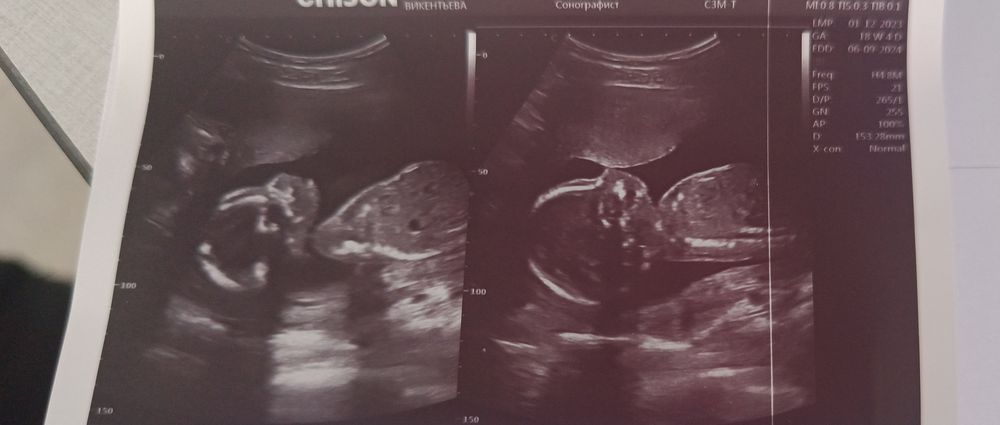

18+4) 266 гр.

УЗИ, КТГ, доплерСегодня нам уже 19 неделя. Сходила на УЗИ, в последнее время затих сынуля пришлось пойти чтобы убедится что все хорошо. Заодно на всякие патологии посмотрели . У нас все отлично. Развиваемся в срок! Весим 266 гр уже, пуповину с шее снял, сб+148